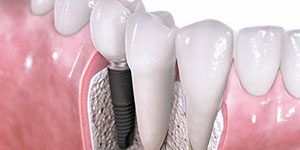

Implantologia

O implante dentário é um dispositivo médico concebido para substitu...